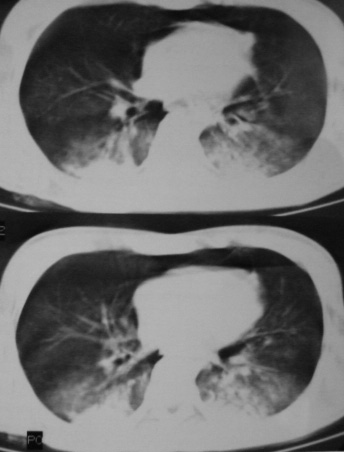

男,18岁,车祸20小时后胸ct.血氧饱和度80,呼吸45次/分.

1:双肺挫裂伤,以双下肺明显。

2:纵隔气肿。

2:纵隔气肿

1.双下肺挫伤;

2.纵隔积气。